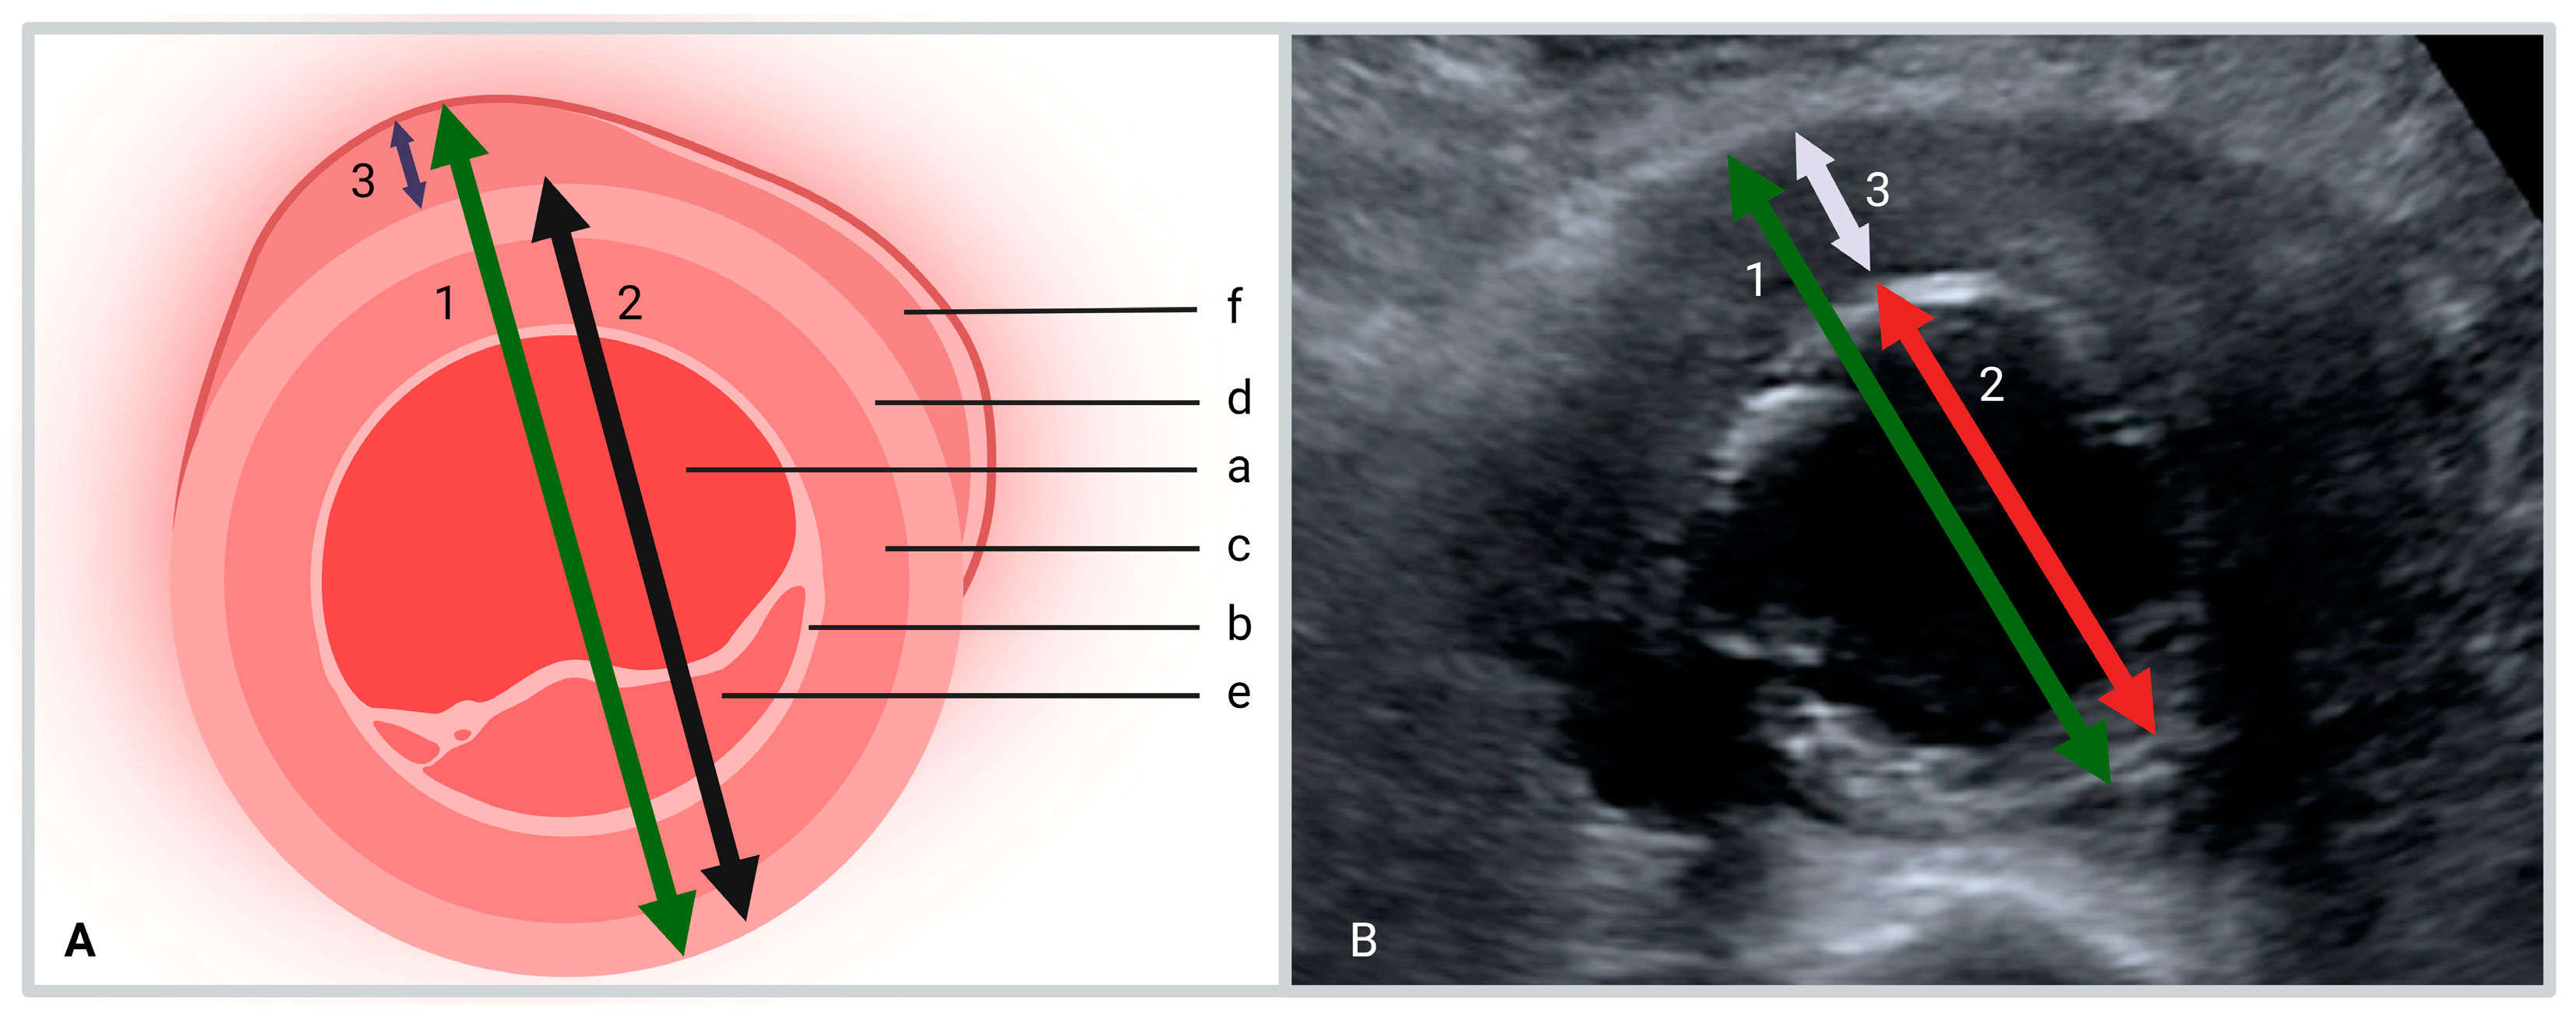

- The maximum anteroposterior diameter of the aorta including the hypo-echogenic layer outside the calcified layer.

- The anteroposterior diameter of the aorta excluding the hypo-echogenic layer (up to the calcified layer)

- The thickness of the hypo-echogenic layer at the anterior site of the aneurysm.